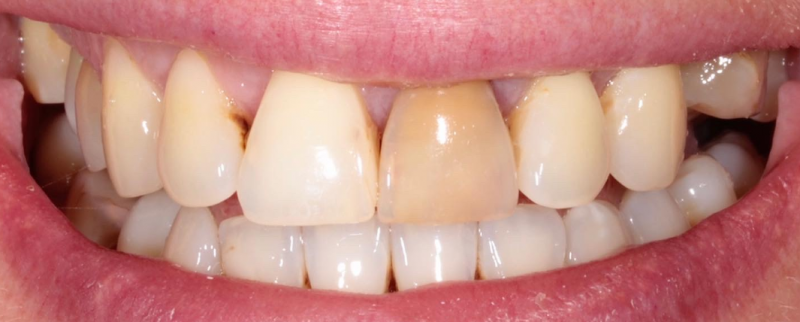

Стоматология ЗУБ (ZUB)

Профгигиена

Все работы клиники